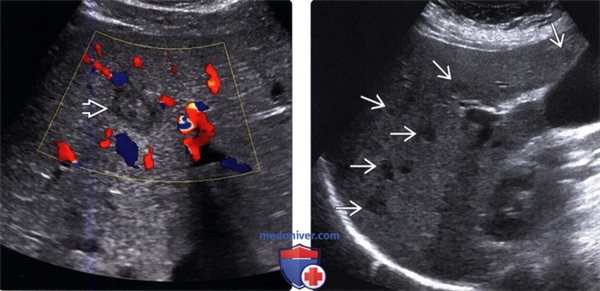

(Левый) Поперечный ультразвуковой срез с цветовой допплерографией. Визуализируется грибковый абсцесс печени с характерным видом круга в круге или мишени. Обратите внимание на отсутствие васкуляризации в грибковом абсцессе.

(Правый) Продольный серошкальный ультразвуковой срез. Визуализируются множественные гипоэхогенные грибковые абсцессы по всей паренхиме печени у пациента с иммунодефицитом.